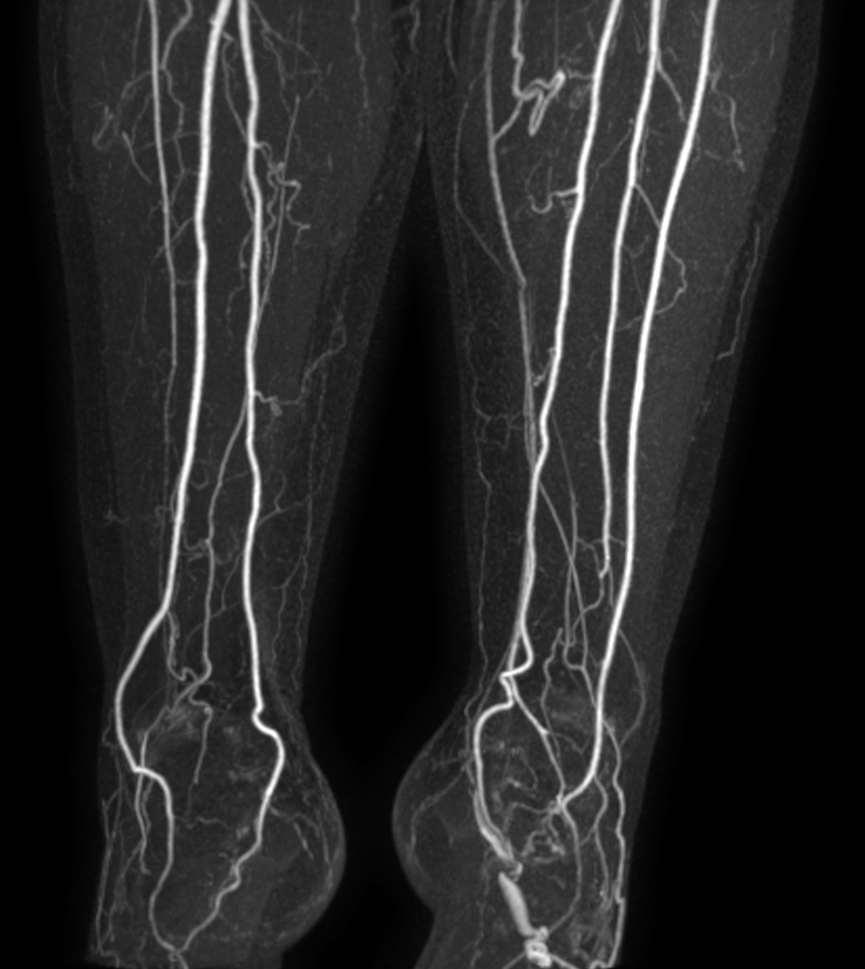

Patient with a known stent in the abdominal veins. Subtraction-less mDIXON MRA run-off is performed using a combination of Compressed SENSE and enhanced gradient strength to increase both in-plane and through-plane spatial resolution. The station covering the feet has been rescanned with a Compressed SENSE factor of 14, resulting in a time resolved scan with a dynamic time of only 4 seconds.

mDIXON MRA (MIP) - Lower leg